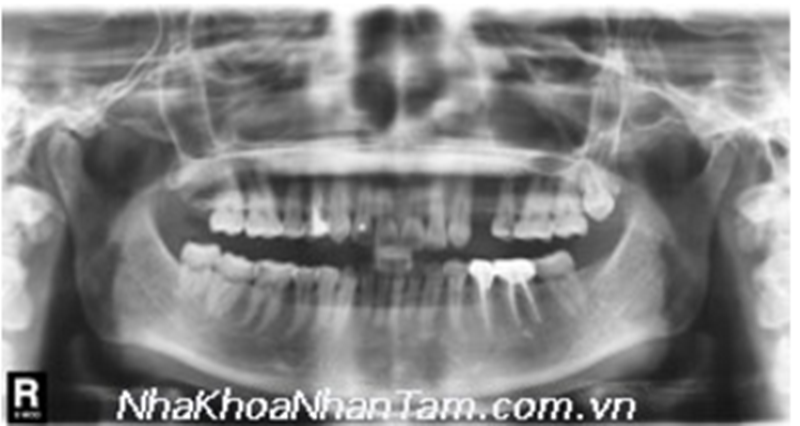

Take x ray to check jawbone density

Panoramic